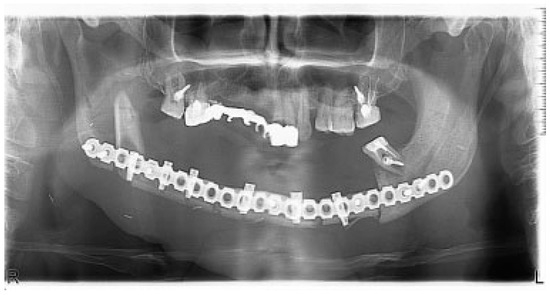

Tomographic Evaluation of Mandibular Thickness on Premolar and Molar Regions Related to Monocortical Screws

The aim of this study was to measure the thickness of the mandible from the external cortical plate to the teeth roots on premolar and molar regions using CT scan to determine the safety margin for the application of monocortical screws for internal...